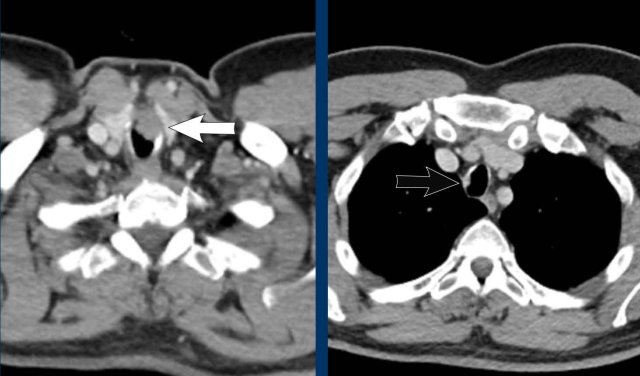

Image

Well-defined mass in the left main

bronchus in a 39 year old male.

Continue with the PET-CT...

The 68Ga-Dotatate PET-CT shows vivid uptake confirming the neuroendocrine cell origin.

On CT carcinoid is a well-defined lesion, often hyperdense on post-contrast CT given their hypervascular nature.

Calcifications may be present in a minority.

Post-obstructive changes are common due to luminal obstruction, and may be the reason it is found.

Some lesions also show an extraluminal component, which excludes the option of complete curation through an endoscopic procedure.